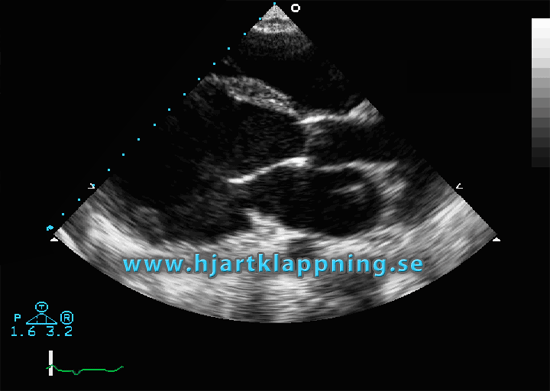

Vid 10- tiden i morse var det dags för Ekokardiografi (EKO). Det gick till som följande:

Jag fick klä av mig på överkroppen och lägga mig på vänster sida på en brits. Det fästes 5 små elektroder på överkroppen och sedan tog man bilder på hjärtat ur olika vinklar med hjälp av ett ultraljud. Hela undersökningen tog cirka en timme för det gällde att få rediga foton från olika håll och kanter med diverse saker såsom till exempel revben i vägen. Jag fick både ligga på vänster sida och på ryggen och de två som hade hand om mig fick trycka ganska hårt för att få till bra skärpa. Var rätt säker på att jag skulle ha blåmärken efteråt men har inte riktigt vågat kika än.

| Detta är inte mitt hjärta, men så här såg jag det på skärmen, fast mitt slog mycket långsammare… Den här googlade bilden verkar vara på någon med ordentlig hjärtklappning. |

Det var häftigt och ganska mäktigt att se sitt eget hjärta pumpa på monitorn. Jag fick se både blodets in- och utflöde samt hjärtklaffarna som jobbade på i maklig takt. Emellanåt fick jag höra hjärtfrekvensen också. Det lät precis som om någon håller upp en tunn skiva av plåt och skakar den i omgångar. Metalliskt.

Inte förrän undersökning var över så berättade man att det man befarat och sökt efter var hjärtsvikt… Anledningen till oron är den vätska vilken jag som bekant verkar samla på mig senaste veckorna och man var tydligen lite rädd för att hjärtat inte pumpade runt som det skulle. Men jag blev snabbt lugnad. Inga tecken på hjärtsvikt!